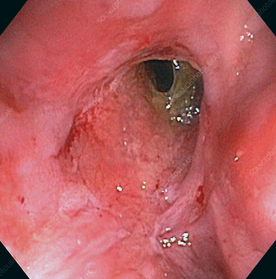

Κολονοσκόπηση. Ευδιάκριτα ευρήματα ισχαιμικής κολίτιδας (Ευγενική παραχώρηση Dr. V. Penopoulos)